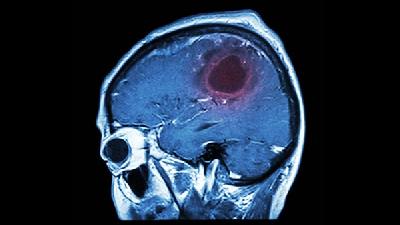

脑萎缩是老年人的常见疾病之一,老年人一旦患有脑萎缩,就会慢慢的丧失生活自主能力,因此一定要及早采取措施预防脑萎缩的发生。那么脑萎缩的预防方法有哪些呢?增加大脑活跃度用进废退,经常读书看报、写写算算,有规律地运转大脑,不断促进大脑神经及感官信息运动的活跃,有利于改善脑部的血液循环,推迟脑细胞的老化,延缓脑萎缩的进程。积极防治血管性疾病脑萎缩的预防应该先预防血管...

小脑萎缩是一种家族显性遗传神经系统疾病,只要亲人中有人患病,其子女将有50%的机率遗传此症并发病。虽然小脑萎缩是遗传性疾病,但是有效的预防可以延缓病情的发展。那么应如何做好小脑萎缩的预防呢?首先,最主要的小脑萎缩的预防方法是一定要吃早餐。占人体体重约2-3%的脑,耗氧量占全身耗氧量的20%-30%,其能量主要来源于葡萄糖的有氧代谢,脑细胞一旦缺乏氧气和能量,...

脑部类的诸多疾病中,脑萎缩的出现就是属于其中之一。在平日里,多加的了解到针对于脑萎缩的预防措施,也是有所必要的。接下来,我们就一起从下面的文章中来了解下吧。1、脑萎缩的预防关键是做到生活规律。调节好正常的生物钟,每天保证7至8小时的睡眠,在良好的环境中劳动、生活,多用脑,但不要有太大的工作压力。2、脑萎缩患者要多参加体育锻炼,运动可以提高机体的循环功能,改善...